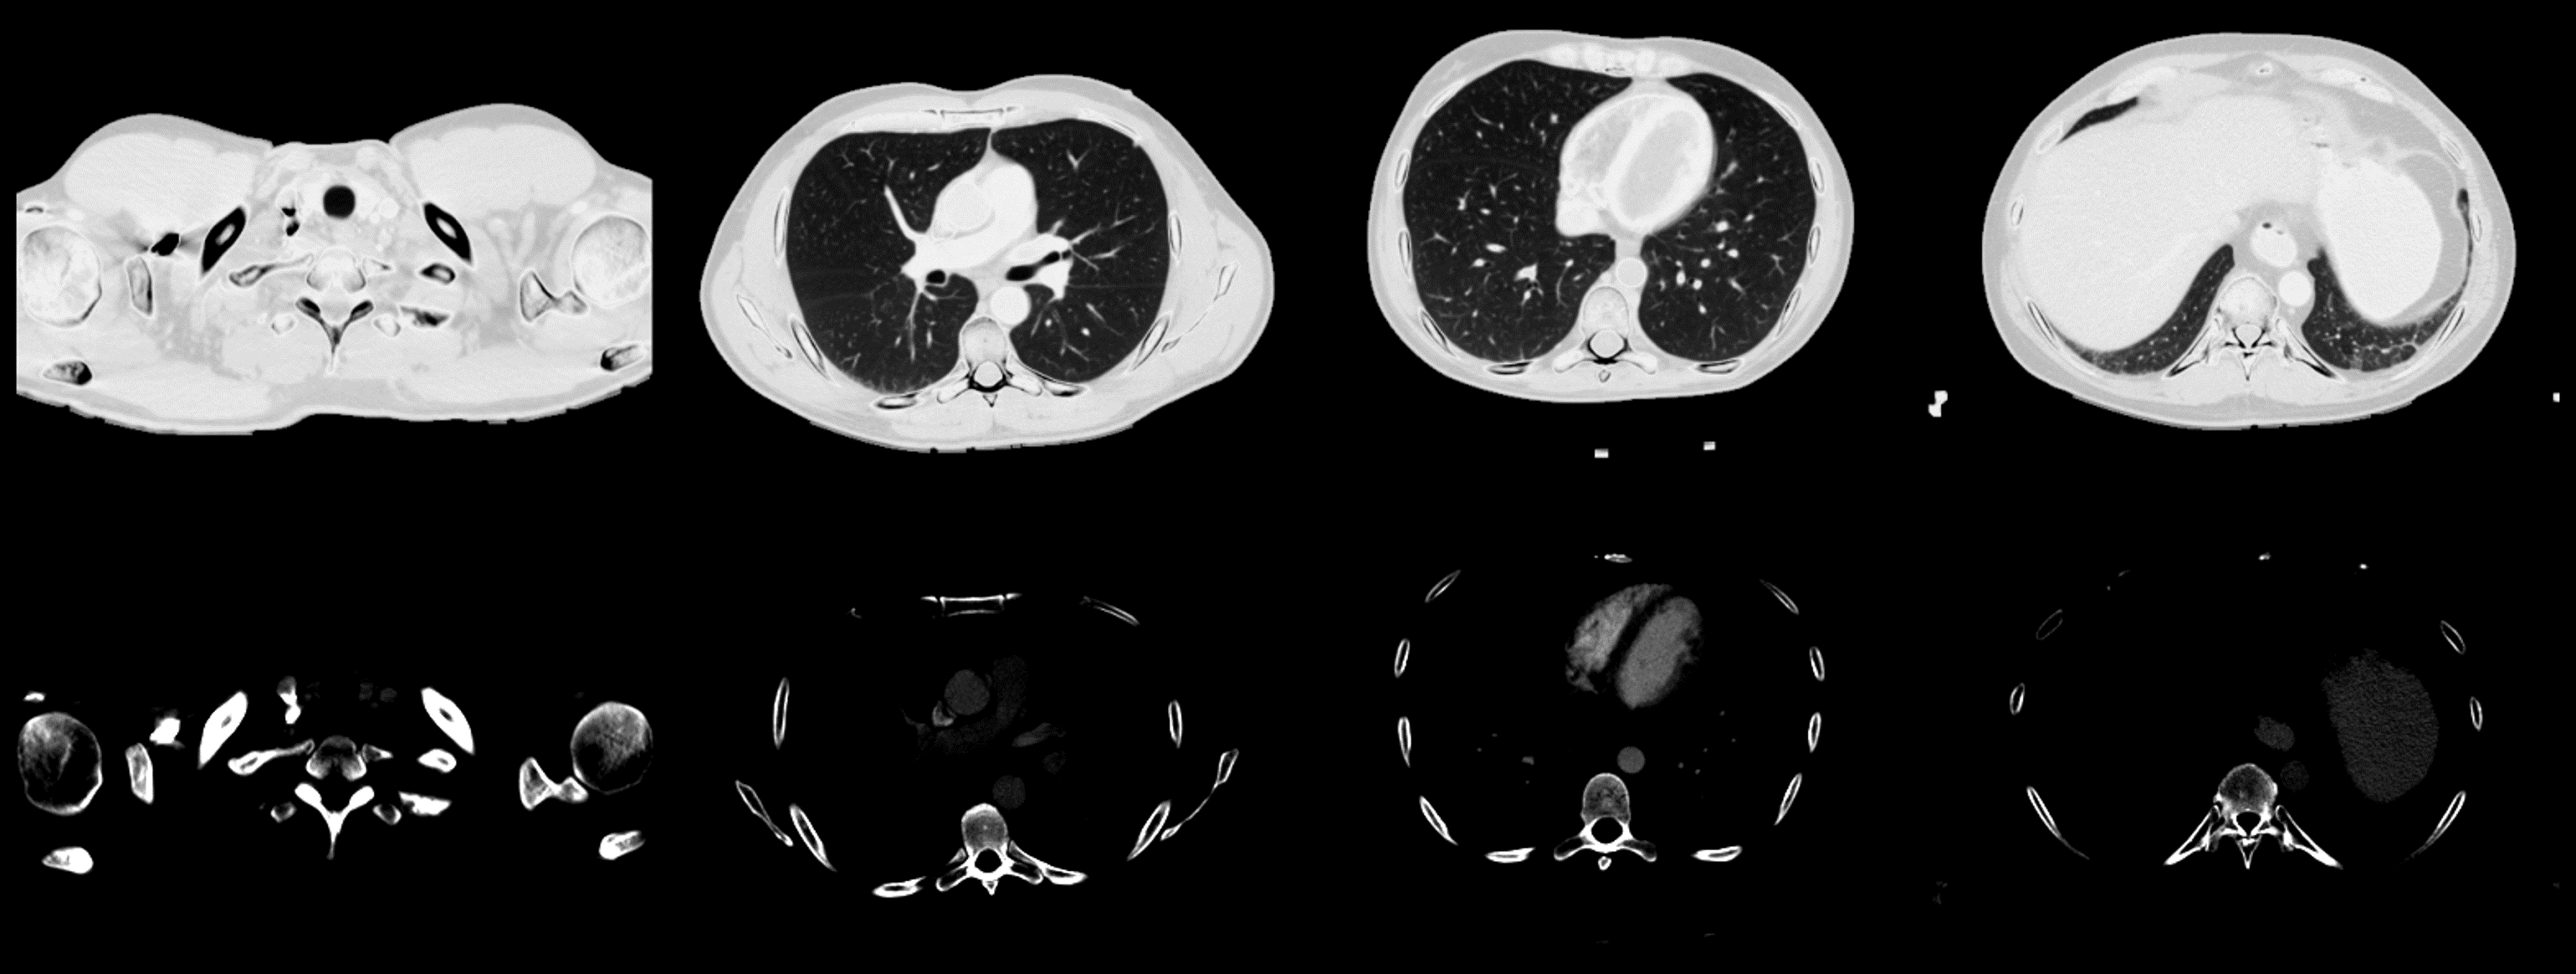

The dataset generation procedure is summarized in Fig.2. We investigated water/calcium decomposition in this work. A two-material dataset was created based on the public CT Lymph Nodes dataset[39], from which chest-region slices were extracted from 150 distinct patients, forming a CT dataset of 30000 slices. Pre-processing includes bed removal via morphological operations and metal reduction via clipping the maximum value to 2000HU. Hounsfield unit values were converted into attenuation coefficients, and then water and calcium densities (unit: g/cm3𝑔𝑐superscript𝑚3g/cm^{3}) were determined by two soft-threshold functions:

Refer to caption

Figure 2: Summary of the processing used to create the two-material dataset from public single-energy CT images.

xw(μ)={kwμ,if μμwkwμwkwc(μμw),if μw<μ<μc0,otherwisesubscript𝑥𝑤𝜇casessubscript𝑘𝑤𝜇if 𝜇subscript𝜇𝑤subscript𝑘𝑤subscript𝜇𝑤subscript𝑘𝑤𝑐𝜇subscript𝜇𝑤if subscript𝜇𝑤𝜇subscript𝜇𝑐0otherwisex_{w}(\mu)=\begin{cases}k_{w}\mu,&\text{if }\mu\leq\mu_{w}\\ k_{w}\mu_{w}-k_{wc}(\mu-\mu_{w}),&\text{if }\mu_{w}<\mu<\mu_{c}\\ 0,&\text{otherwise}\end{cases} (10a)

xc(μ)={kc(μμc)+kcw(μcμw),if μμckcw(μμw),if μw<μ<μc0,otherwisesubscript𝑥𝑐𝜇casessubscript𝑘𝑐𝜇subscript𝜇𝑐subscript𝑘𝑐𝑤subscript𝜇𝑐subscript𝜇𝑤if 𝜇subscript𝜇𝑐subscript𝑘𝑐𝑤𝜇subscript𝜇𝑤if subscript𝜇𝑤𝜇subscript𝜇𝑐0otherwisex_{c}(\mu)=\begin{cases}k_{c}(\mu-\mu_{c})+k_{cw}(\mu_{c}-\mu_{w}),&\text{if }\mu\geq\mu_{c}\\ k_{cw}(\mu-\mu_{w}),&\text{if }\mu_{w}<\mu<\mu_{c}\\ 0,&\text{otherwise}\end{cases} (10b)

The parameters, kwsubscript𝑘𝑤k_{w}, kwcsubscript𝑘𝑤𝑐k_{wc}, kcwsubscript𝑘𝑐𝑤k_{cw}, kcsubscript𝑘𝑐k_{c} were empirically set to 5.185.185.18, 8.778.77-8.77, 5.695.695.69, 2.12g/cm22.12𝑔𝑐superscript𝑚22.12~{}g/cm^{2}, while μwsubscript𝜇𝑤\mu_{w} and μcsubscript𝜇𝑐\mu_{c} were 0.22cm10.22𝑐superscript𝑚10.22~{}cm^{-1} and 0.35cm10.35𝑐superscript𝑚10.35~{}cm^{-1}. Fig.3 illustrates example images in the synthetic two-material dataset. Part of the soft tissue, notably in the heart region, exhibits high intensity in the calcium images because of iodine contrast enhancement.